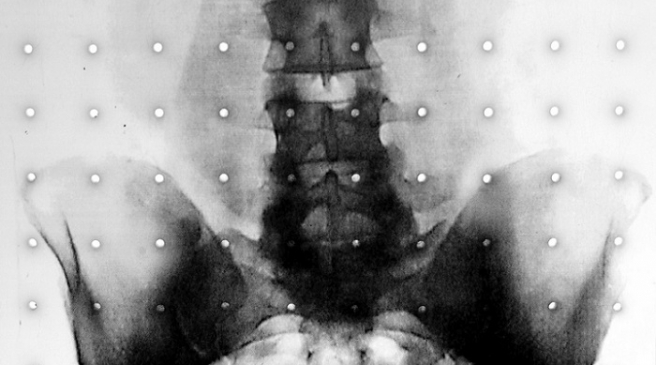

Problem sa sakroilijakalnim zglobom, SI, mjestom raskrižja u bazi kičme koji povezuje kičmeni stup s kostima zdjelice, spada u ovu drugu kategoriju uzroka križobolje, kaže dr. David Bornstein, reumatolog i profesor na sveučilištu George Washington. “Sakroilijakalni zglob je čest uzrok boli u lumbalnom dijelu leđa ali nije uvijek prepoznat i liječnici ga zamijene za druge uzroke križobolje.”

Tijelo ima dva sakroilijakalna zgloba, sa svake strane kičme. Uloga tog zgloba je da amortizira udarce i podupire težinu gornjeg dijela tijela, dok ostaje relativno stabilan. On nije kao koljeno ili lakat koji se savijaju naprijed natrag, nego je zglob koji se ne pomiče puno odnosno nije predviđeno da se pomiče.

Krut i slabo pokretan, male amplitude pokreta, predstavlja mjesto povezivanja kičmenog stupa i donje polovice tijela. Minimalna pokretljivost između kostiju koje spaja stvara velike sile opterećenja koju trpe strukture ovog zgloba. Disfunkcija ovog zgloba česti je uzrok boli u donjem dijelu leđa, stražnjici i preponama. Pacijentima je teško dulje stajati ili se penjati uz stepenice, trčati, raditi veće korake, savijati se, sjediti dulje vrijeme, skakati. Bol može obuhvatiti i noge, prepone pa i stopala.

U posljednje vrijeme bol se rješava kirurškom intervencijom koja znači ulaganje malog implantata u zglob, a to efikasno smanjuje bol i poboljšava pacijentovu pokretljivost. Novim postupkom se u zglob postavlja trokustati titanski implantat, kroz maleni rez, na taj se način zglob stabilizira i bol prestaje.